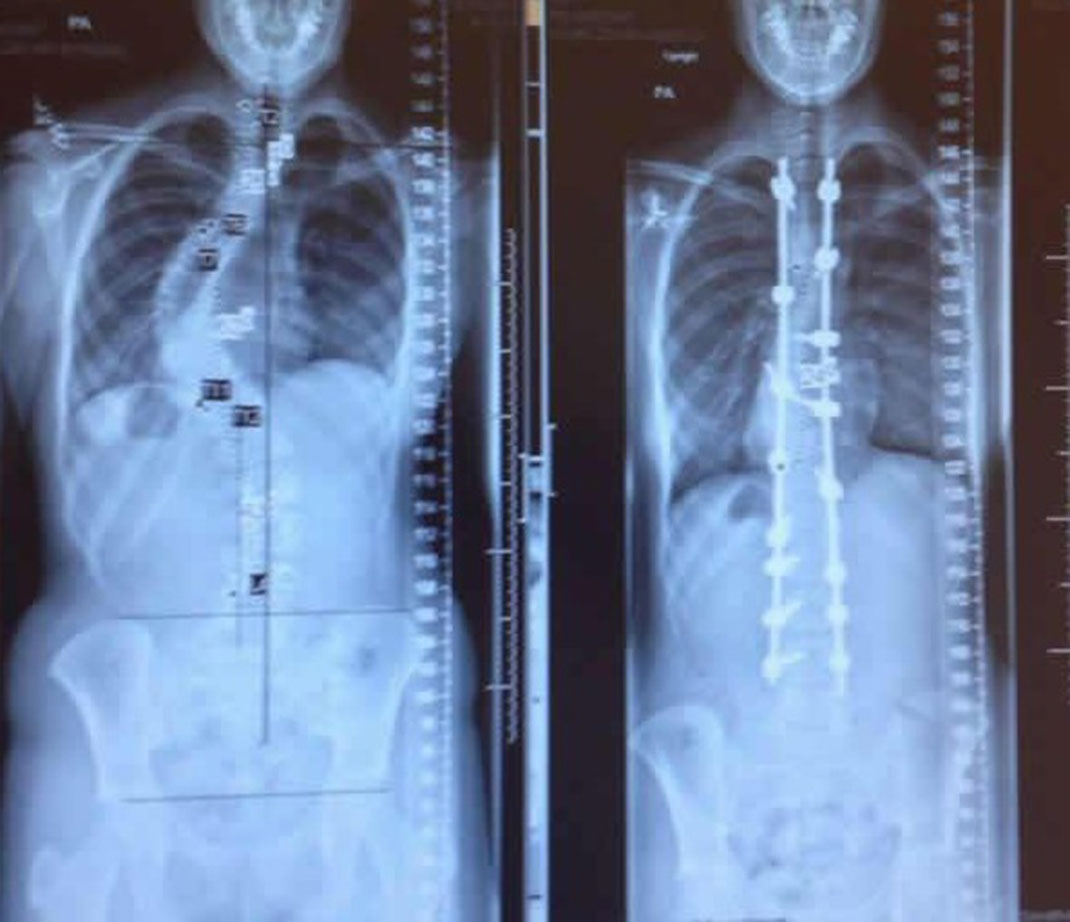

1) Une radio avant et après un traitement pour la scoliose